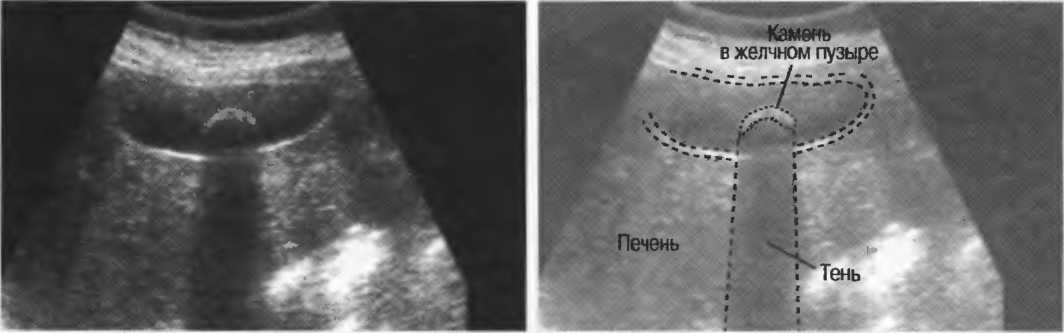

Рис. 17а. Большая акустическая тень за камнем в желчном пузыре.